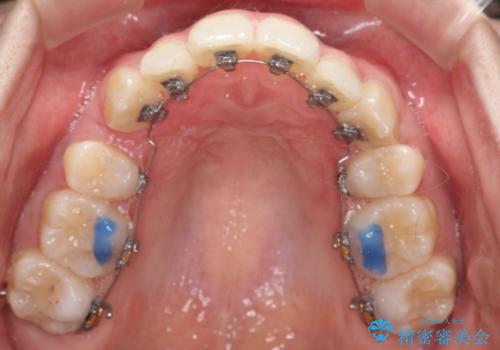

- ハーフリンガル

- 2年1ヶ月

目立たない装置をご希望でしたので、上下左右の歯を1本ずつ抜歯してハーフリンガルでの矯正を行いました。